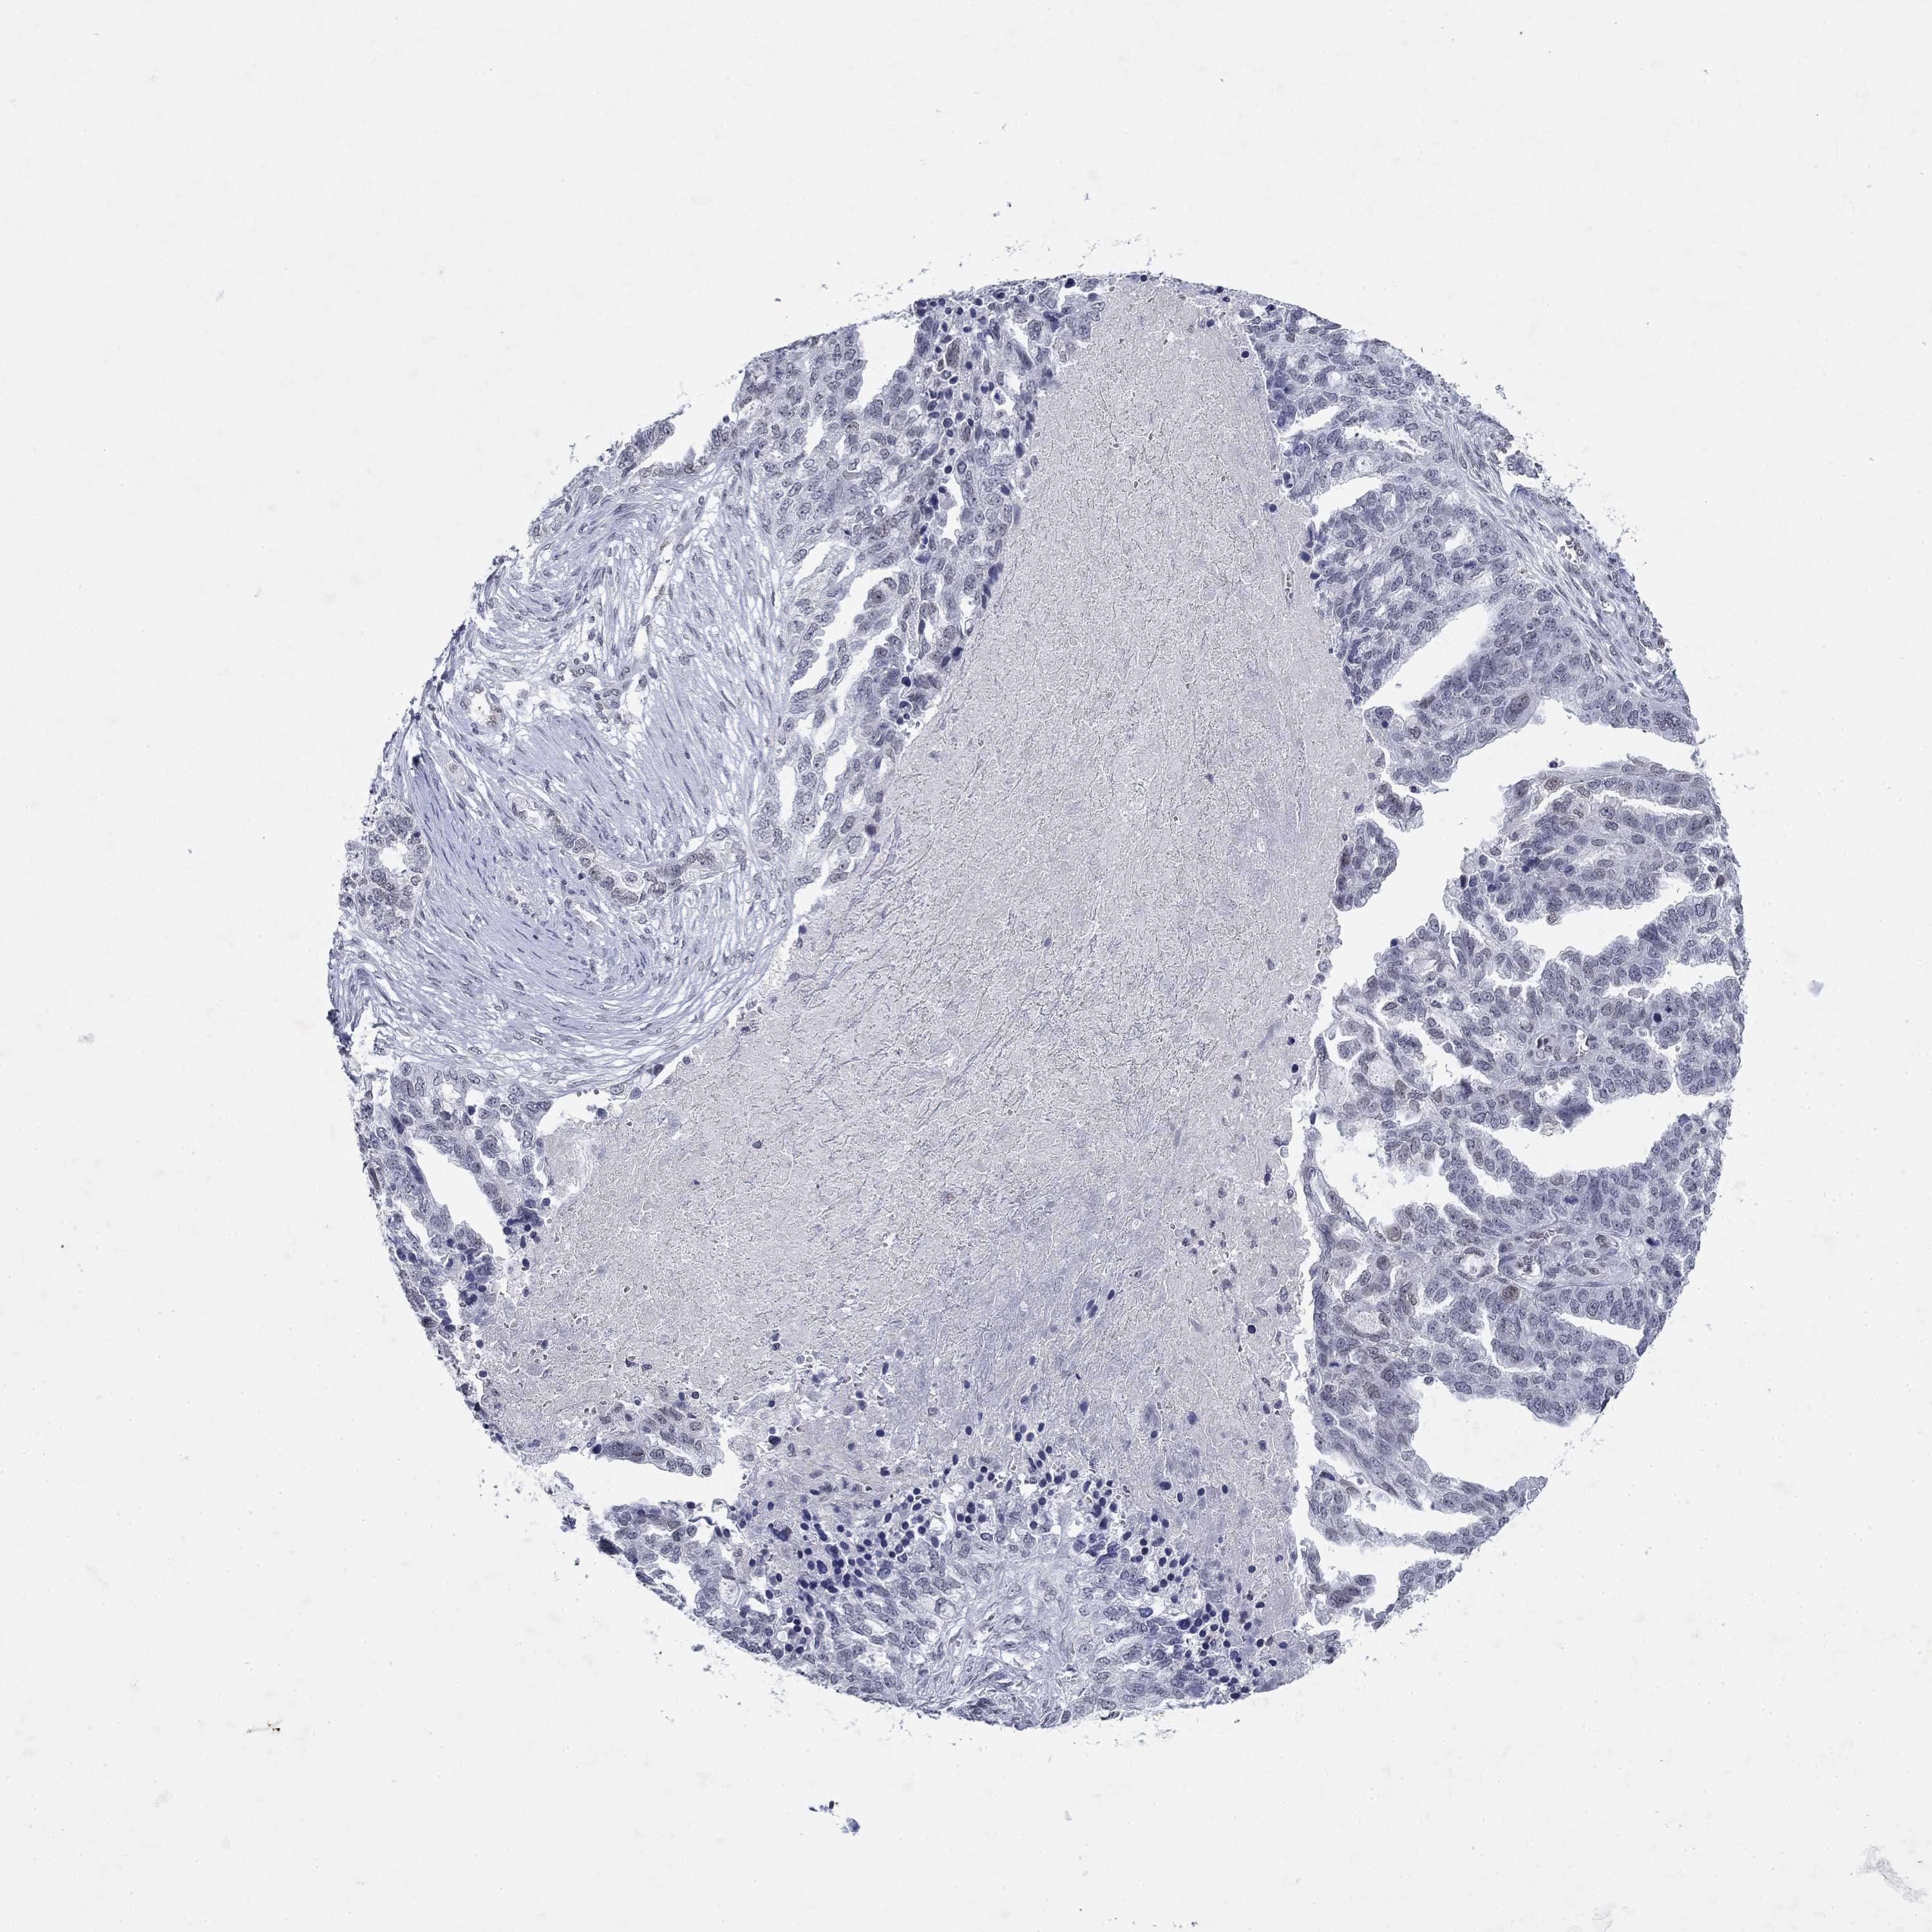

OVARIAN CANCER - Protein expressioni

A mouse-over function shows sample information and annotation data. Click on an image to view it in a full screen mode. Samples can be filtered based on level of antibody staining by selecting one or several of the following categories: high, medium, low and not detected. The assay and annotation is described here.

Note that samples used for immunohistochemistry by the Human Protein Atlas do not correspond to samples in the TCGA dataset.

Antibody stainingi

Antibody staining in the annotated cell types in the current human tissue is reported as not detected, low, medium, or high, based on conventional immunohistochemistry profiling in selected tissues. This score is based on the combination of the staining intensity and fraction of stained cells.

Each image is clickable and will lead to virtual microscopy that enables deeper exploration of all samples and also displays staining intensity scores, fraction scores and subcellular localization as well as patient and tissue information for each sample.

Antibody HPA047151

Cystadenocarcinoma, serous, NOS

Carcinoma, endometroid

Cystadenocarcinoma, mucinous, NOS

Carcinoma, NOS